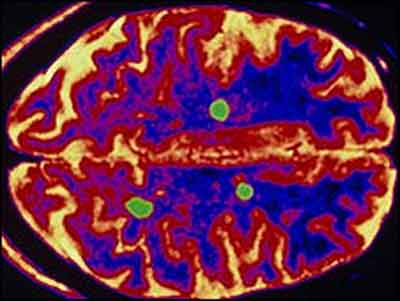

Multiple Askloroses K Mareezon K Liay Umeed